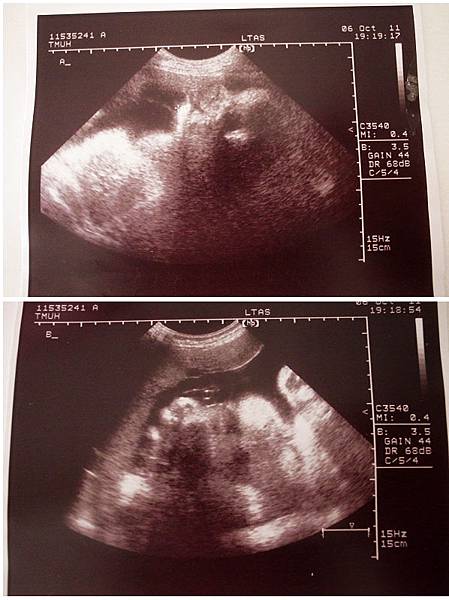

(大小福臉部特寫)

產檢日期:10/06/2011

產檢醫院:台北醫學院(沒錯大小福要回北醫生了)

產檢結果:

大福頭朝下位置已經很低了,體重測量會有比較大的誤差,大約20002200g

小福頭朝上,胎位不正,體重約22002400g

從照片來看大福似乎有個大鼻子小福有個胖胖臉哈哈